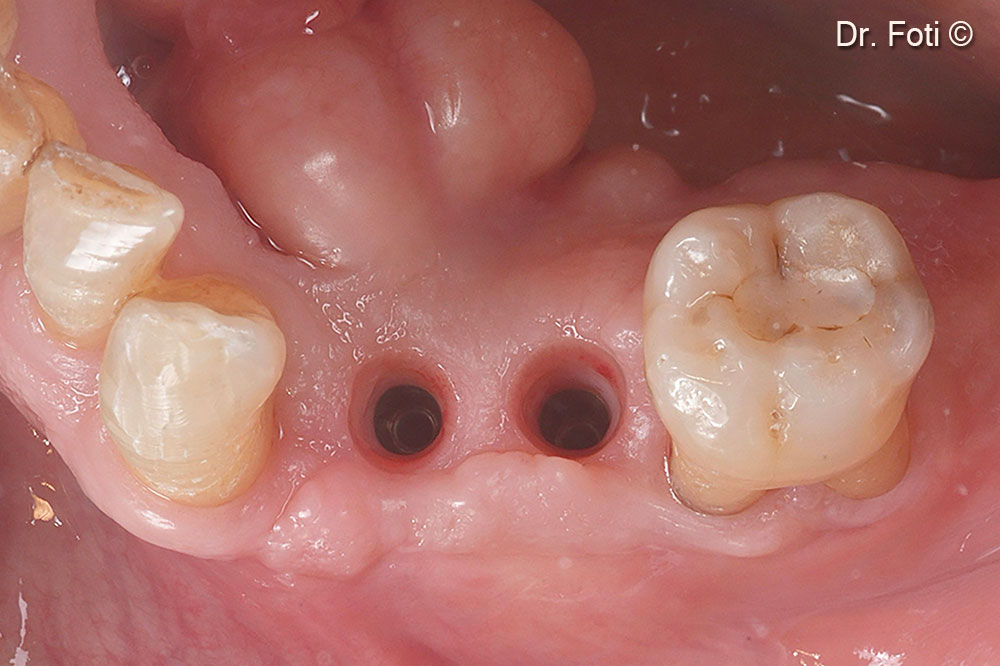

Two healing abutments are placed six months after the surgery